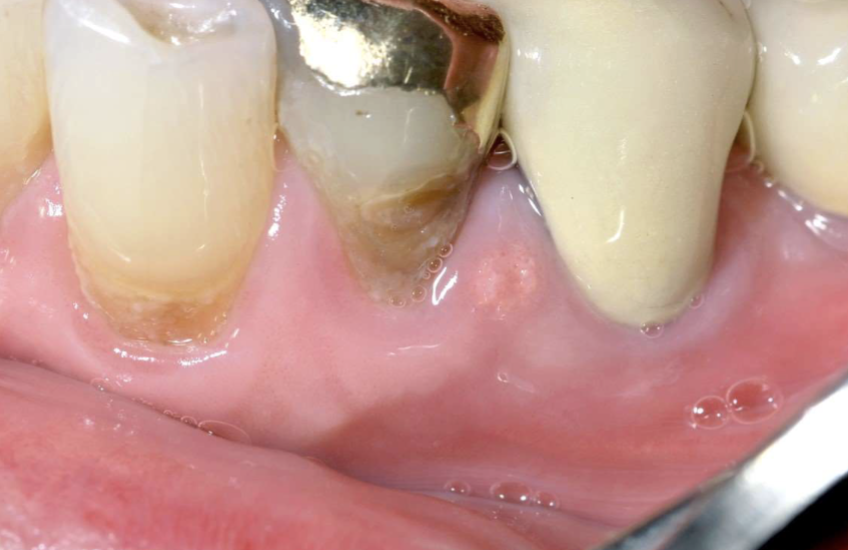

what is this

verruciform xanthoma